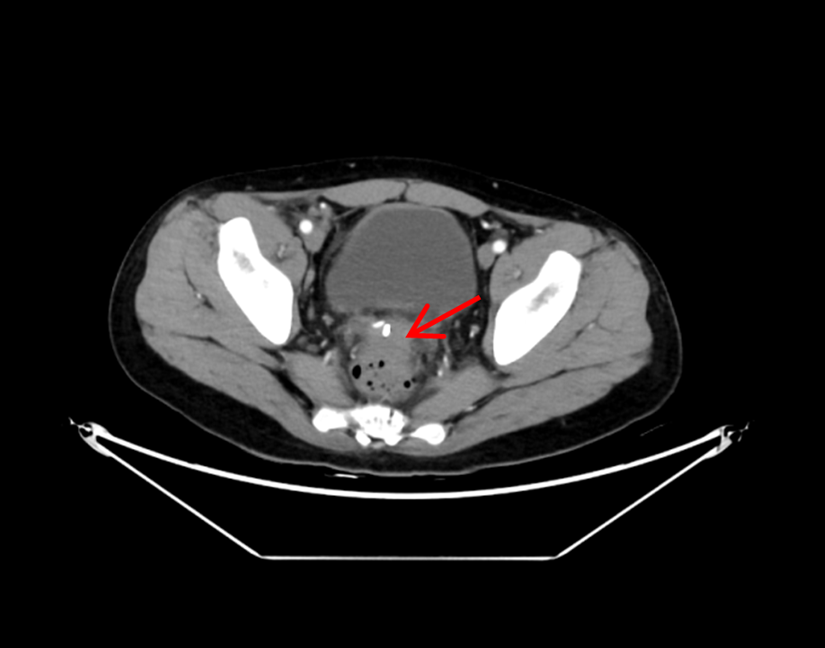

术后4天复查CT显示脓肿基本消失

术后4小时,大量脓液即经肛门顺利排出,患者发热症状消退;术后2天,尿频、尿急、肛门下坠等不适症状完全缓解;术后4天复查CT显示,盆腔脓肿已基本消退;术后5天,患者顺利康复出院。出院前,患者含泪对医护团队表达感谢:“医者仁心,你们不仅治好了我身体的病痛,更治愈了我心底的恐慌,感谢青大附院的医护人员们。”